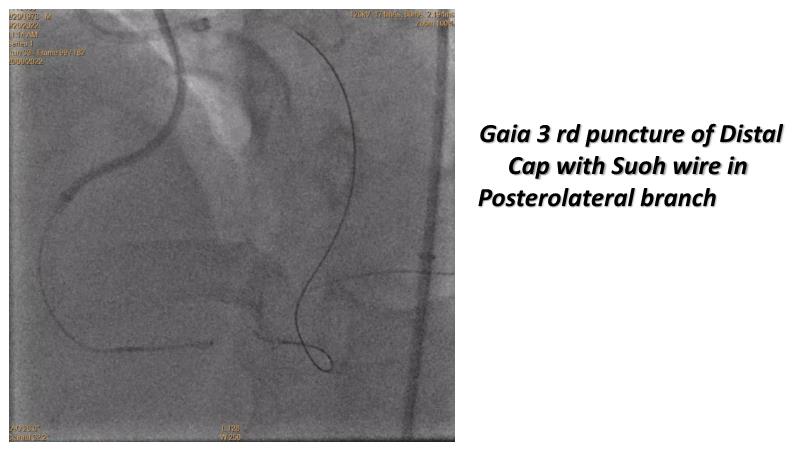

Thanks to the recorded complex CTO case shared in this session, learn how to perform ultra-low contrast PCI, learn what skills are required and tools available to perform ultra-low contrast coronary interventions in CTO, and become aware of the importance of relying on less contrast injections to guide PCI in complex CTO cases.